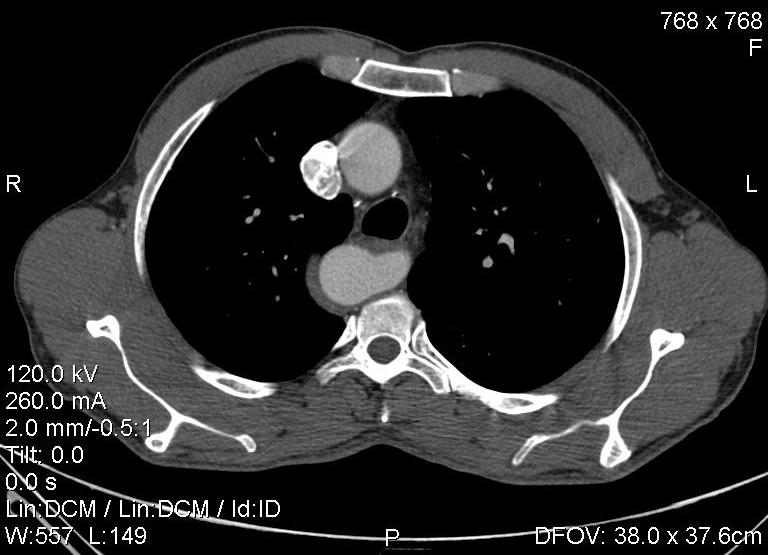

Пациент был направлен на КТ после рентгенографии ОГК, с направительным диагнозом: объёмное образование верхнего средостения.

Конечно, дуга аорты идёт справа от позвоночника (декстра позиция); но есть и ещё одна аномалия той же группы: